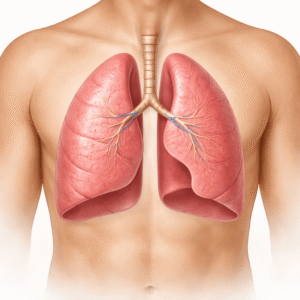

Stop Smoking Aids

Types of Stop Smoking Aids: Nicotine Replacement Therapy (NRT): Provides…

What Are the Best COPD Treatment Options for You?

COPD can feel like a battle with every breath. If you or…

Asthma: A Complete Guide to Causes, Symptoms, Diagnosis, and Treatment

Asthma is a chronic respiratory disease affecting more than 260 million people…

Asthma Control: Daily Tips for Better Breathing

Asthma affects millions worldwide, but with the right strategies, symptoms can be…